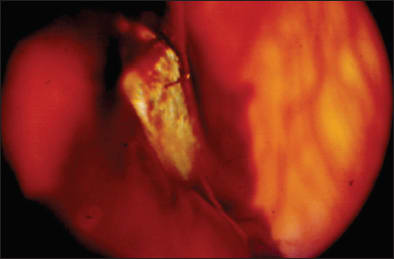

Young men are most prone to sustaining open-globe injuries with retained IOFBs, with the majority of injuries occurring at the workplace. Hammering, using machine tools, shooting weapons and being in proximity to explosions are among the most common mechanisms involved in retained IOFB cases. Less common causes include assault, motor vehicle accidents, lawn mower injuries and insect stings. The foreign bodies produced by hammering tend to be small, sharp projectiles that penetrate the eye with less disruption and carry a more favorable prognosis (Figure 1). Roughly 90% of the involved projectiles are metallic, and over half of these are magnetic. The other mechanisms of injury tend to produce projectiles that are larger and blunter, consequently causing more damage to the eye on penetration, oftentimes leading to a more guarded visual prognosis.3-5

Figure 1. An intravitreal metallic IOFB with a moderate amount of vitreous hemorrhage, which was sustained while hammering metal on metal. The IOFB was removed via pars plana vitrectomy techniques and an internal magnet and forceps. The final visual outcome was 20/20.